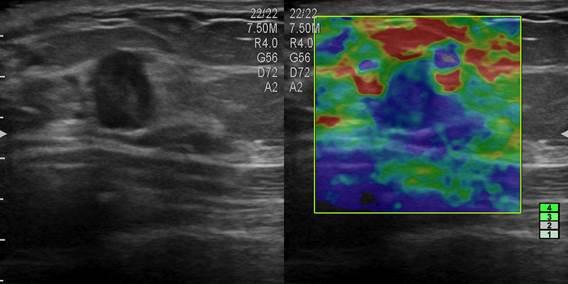

Ung thư tuyến vú

Ung thư tuyến vú - Ảnh 5

» Thông tin: Nữ giới – 45 tuổi.

» Lâm sàng: Kiểm tra sức khỏe.